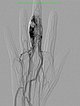

Das Rezidiv der AVM hier in der vergrößerten Zielaufnahme des D III während der Angiographie mit deutlicher Vergrößerung im Vergleich zu den alten Angiographien (nicht abgebildet). Die DSA-Aufnahmen nach transarterieller antegrader Punktion der Arteria brachialis zeigen eine hypervaskularisierte AVM von Fingermittel und -endglied.

Fluoroskopische Darstellung der Punktionsnadel bei Beginn der direkten perkutanen Embolisationstherapie am Finger mit einem Flüssigembolisat (EVOH). Zusätzlich sichtbar der nicht ganz bis zum Nidus vorgeschobene Mikrokatheter.

Fluoroskopische Abschlußkontrolle nach erfolgreicher Nidusembolisation der AVM. Der transarteriell von brachial eingebrachte Mikrokatheter wurde während der perkutanen Embolisation als Landmarke für die zuführende Arteria digitalis propria belassen. Zusätzlich sichtbar röntgendichte Markierungen durch auf der Haut aufliegende Kompressen.